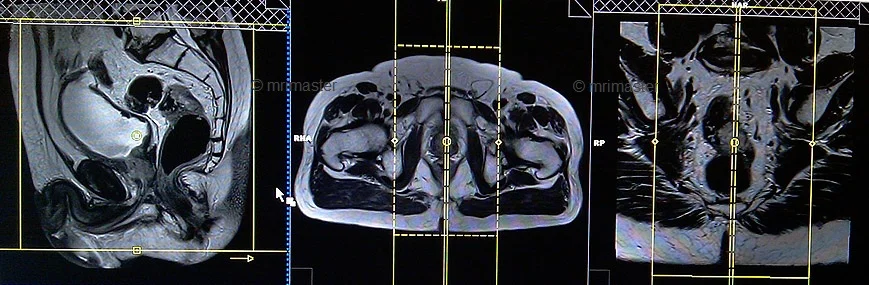

T2 tse axial oblique 3mm SFOV

Plan the axial oblique slices on the sagittal plane. Align the position block perpendicular to the rectum, taking care to position the axial slice precisely perpendicular to any visible cancer within the rectum. Verify the positioning block’s alignment in the other two planes. Ensure an appropriate angle in the coronal plane, also perpendicular to the rectal cancer. Adjust the number of slices to cover the entire rectal cancer adequately. To minimize artifacts caused by arterial pulsation, peristalsis, and breathing, consider adding saturation bands on top and anterior to the axial block.

Parameters

T2 tse coronal oblique 3mm SFOV

Plan the coronal oblique slices on the sagittal plane and angle the positioning block parallel to the rectum. It is essential to align the coronal slice parallel to any visible cancer within the rectum. Check the positioning block in the other two planes. In the axial plane, ensure an appropriate angle is given either horizontally across the rectal cancer or parallel to the right and left hip joint. The slices must be sufficient to cover the entire rectum and pre-sacral space from the symphysis pubis up to the sacrum, as it is crucial to include the lymph nodes in the pre-sacral space. To reduce artifacts from arterial pulsation, peristalsis, and breathing, consider adding saturation bands on top and in front of the coronal block.